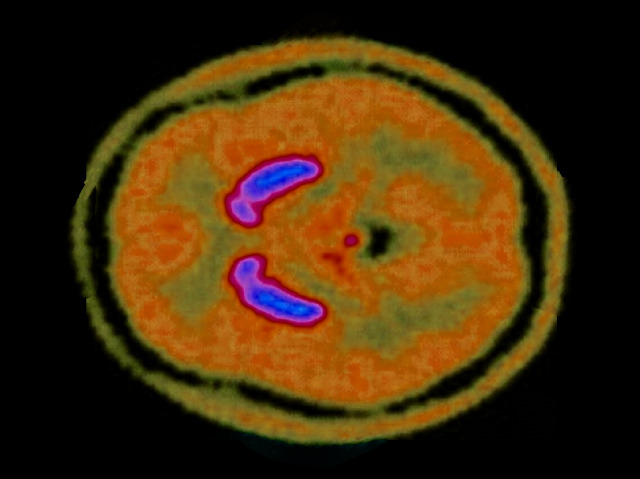

Schizophrenia Awareness Week Dopamine Dip

Dopamine Dip

Cannabis is the most widely-used of illegal substances. The active component of the plant, tetrahydrocannabinol (THC), meddles with the chemical balance of our brains inducing memory loss and anxiety. Studies have linked cannabis use to mental disorders such as schizophrenia and depression. Regular users, who experienced psychotic-like symptoms while under the influence, were the subject of a recent investigation into the effects of cannabis on the brain. The study found that smoking cannabis often tends to lower levels of the brain chemical dopamine in the striatum (purple-blue), as shown in this scan. Low dopamine is associated with low levels of motivation. The good news is that this effect was found to be reversible.